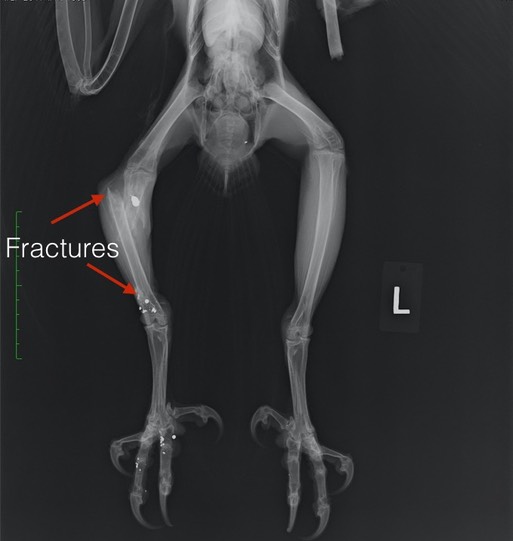

Great Horned Owl 20-020 is the fifth gunshot bird admitted this year. He was found near Yakima with a humerus fracture that was non-repairable and two fractures in his right tibiotarsus. At 16.2 mcg/dl, his blood lead level was the highest we have measured in a Great Horned Owl.